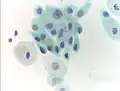

- Micrograph of a normal pap smear

- Micrograph of a Pap test showing a low-grade intraepithelial lesion (LSIL) and benign endocervical mucosa. Pap stain.

- Micrograph of a Pap test showing trichomoniasis. Trichomonas organism seen in the upper right. Pap stain.

-

- Endocervical adenocarcinoma on a pap test.

- Candida organisms on a pap test.

- Viral cytopathic effect consistent with herpes simplex virus on a pap test.

- Normal squamous epithelial cells in premenopausal women

- Atrophic squamous cells in postmenopausal women

- Normal endocervical cells should be present into the slide, as a proof of a good quality sampling

- The cytoplasms of squamous epithelial cells melted out; many Döderlein bacilli can be seen.

- Infestation by Trichomonas vaginalis

- An obviously atypical cell can be seen